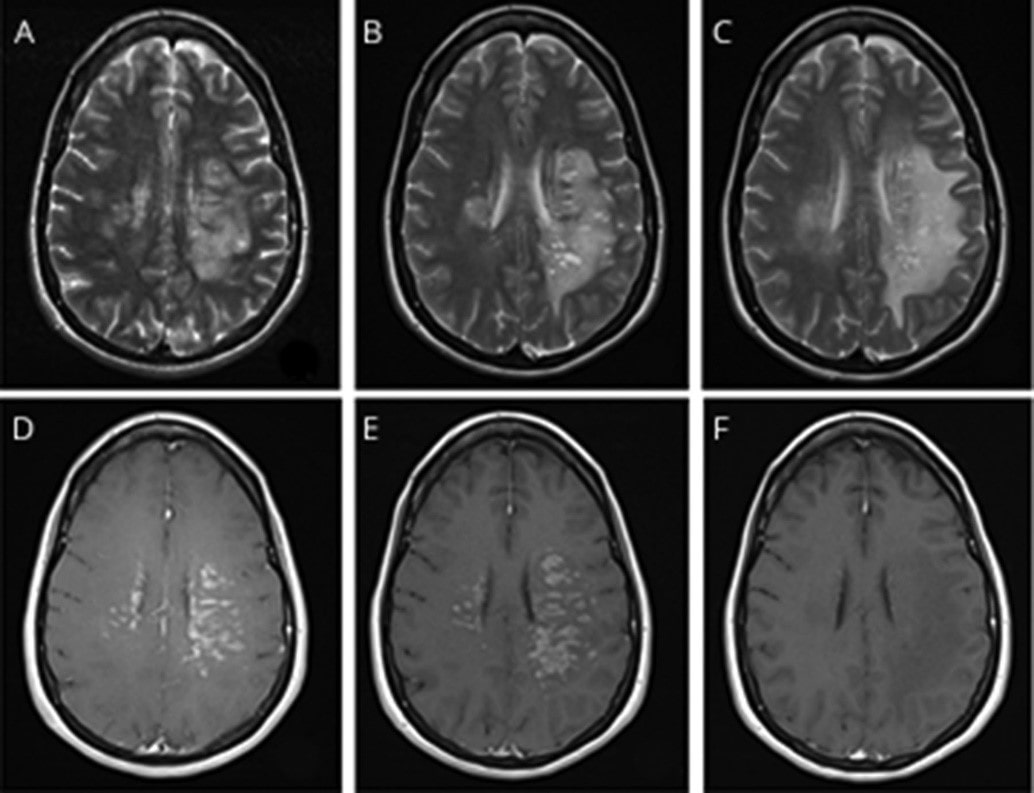

Brain vessel damage due to COVID-19 and resolution after COVID treatment

At last estimate, 5% to 35% of COVID patients suffer these symptoms. A June 2020 paper in Neurology reported that some patients with COVID-19 illness exhibit signs of brain damage or brain injury (though authors believe this is uncommon). These symptoms could include coma, seizures, limb sensory abnormalities, paralysis, decreased consciousness and decreased cognition. The neuropsychiatric fallout of COVID-19 has been PTSD, fatigue, cognitive impairments, decreased memory, decreased attention, and psychiatric impairment. It is unknown whether most patients will gradually recover or whether some will have lifetime effects.